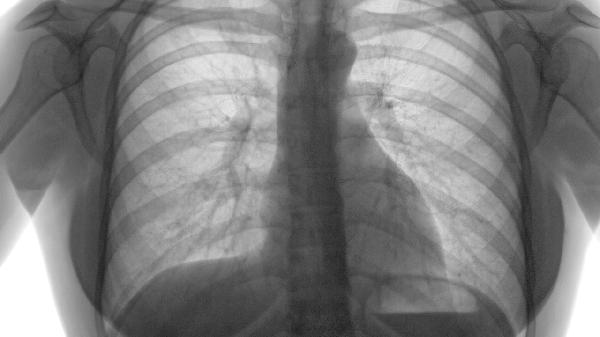

肺气肿属于慢性阻塞性肺疾病,其病理改变是肺泡壁破坏而非细胞异常增生,故不会直接转化为肺癌。但长期炎症刺激和吸烟等共同危险因素,可能使肺气肿患者肺癌发生率较常人升高2-3倍。定期低剂量CT筛查对重度吸烟合并肺气肿者尤为重要。

轻度肺气肿患者10年生存率接近正常人,而极重度患者5年生存率不足50%。预后与FEV1值显著相关,当FEV1低于35%预计值时,可能并发肺心病等严重并发症。

除常规肺功能检查外,需警惕体重下降、咯血等肺癌预警症状。合并肺大疱者需预防自发性气胸,血氧饱和度持续低于88%应考虑长期氧疗。每年至少进行1次全面评估。